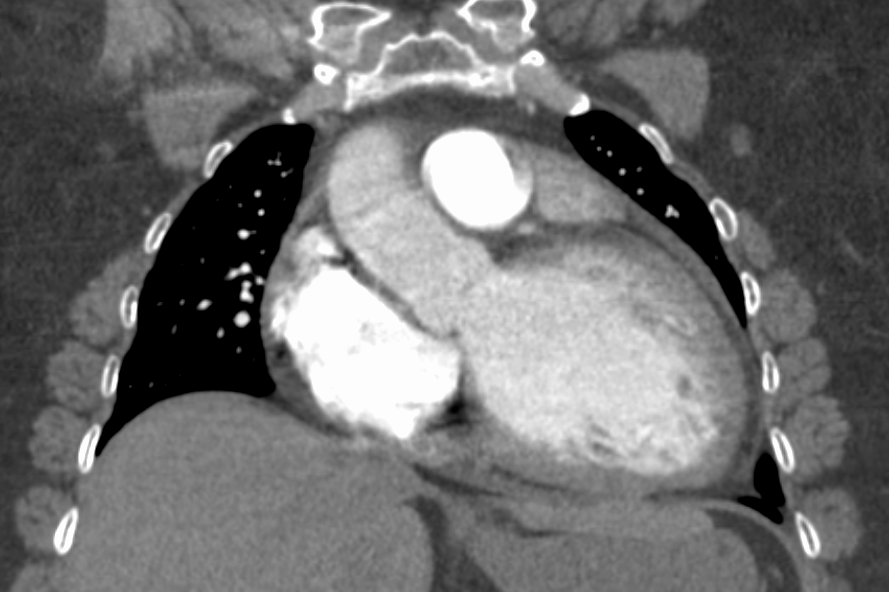

심전도는 종종 동성 빈맥 또는 심방 세동, 심실 부정맥, 좌심방 비대를 나타내며 때로는 심실 내 전도 결함 및 낮은 전압을 보이기도 한다. 좌각 차단(LBBB)에 우측 축 편위(RAD)가 동반되는 드문 조합은 확장성 또는 울혈성 심근병증을 강력하게 시사하는 것으로 간주된다.[29][30] 심장 초음파는 정상 또는 얇아진 벽과 감소된 박출 계수를 가진 좌심실 확장을 보여준다. 허혈성 심장 질환을 배제하기 위해 심장 도관 삽입술 및 관상동맥 조영술을 자주 시행한다.[28]

확장성 심근병증, CT 촬영